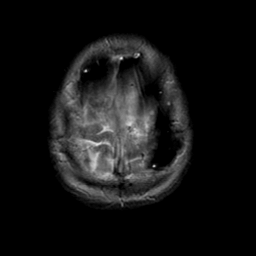

Meningioma, MR Study #2 -- Slice #19

[Home][Help][Clinical] Slice 19